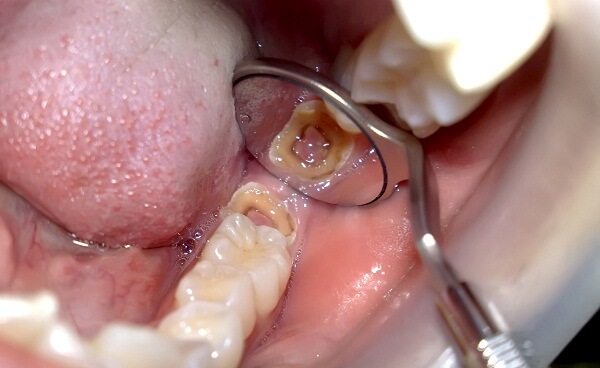

Sâu răng bắt đầu bằng việc xâm nhập vào lớp men răng, sau đó lan vào ngà răng và cuối cùng là tủy răng. Ngà răng, do cấu trúc không cứng bằng men răng, dễ bị tổn thương hơn và sâu răng có thể phát triển nhanh chóng. Khi ngà răng bị sâu, cơ thể sẽ phản ứng bằng cách tạo ra lớp “ngà phản ứng” để bảo vệ các dây thần kinh khỏi các kích thích có hại.

- Mức độ tổn thương: Nếu sâu chỉ ảnh hưởng đến lớp men răng, có thể điều trị bằng lấp phủ composite để giữ lại răng.

- Sâu răng và tình trạng tủy: Nếu sâu đã lan rộng vào tủy, cần phải nhổ răng để ngăn ngừa lây nhiễm.